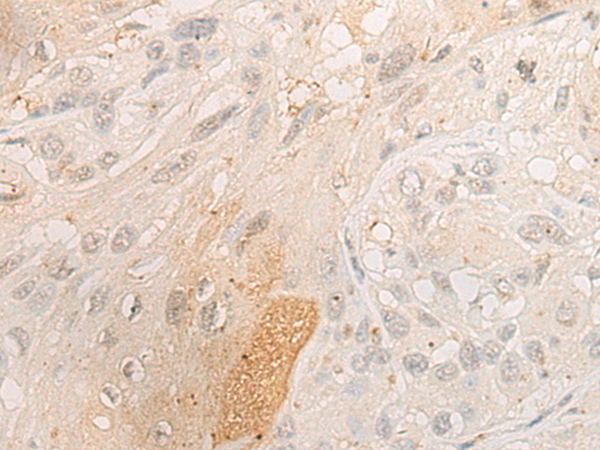

分类: 科研抗体货号: P06385别名: SCDO1应用: IHC反应种属: Human